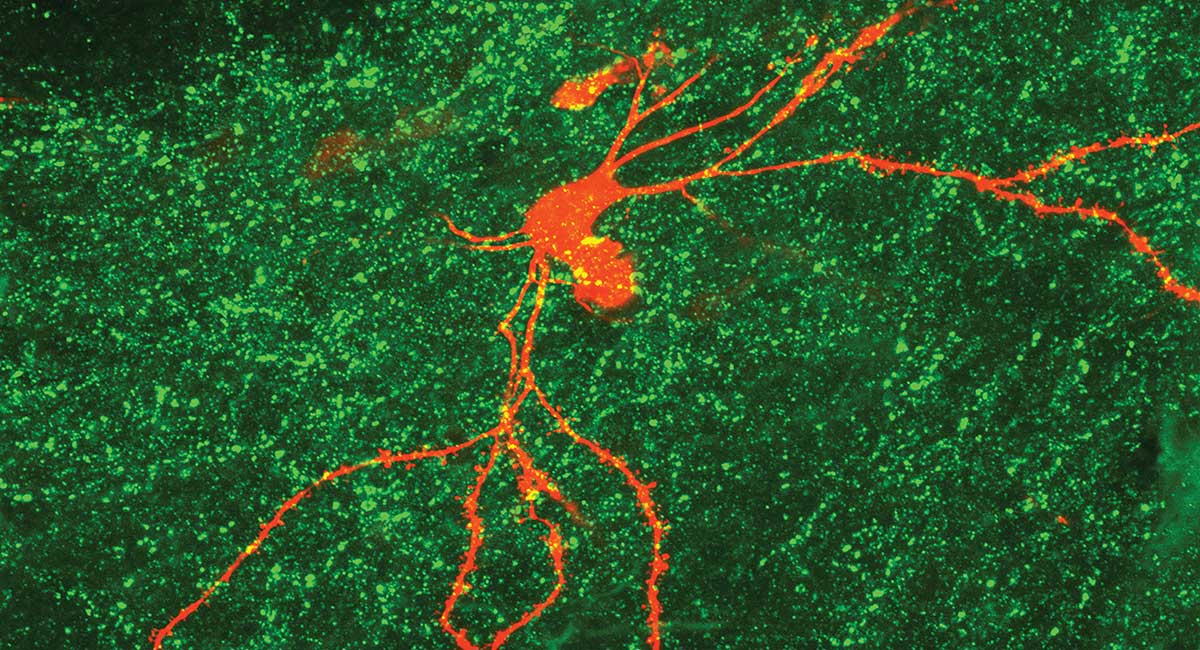

Neurons in the hypothalamus responsible for regulating the body's circadian rhythms.

Neurons in the brain